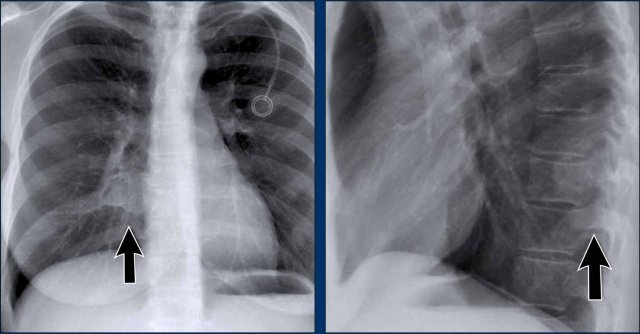

Bochdalek hernia Bochdalek hernia

Congenital Diaphragmatic Hernias

Bochdalek Hernia

• A Bochdalek hernia is a common incidental finding in adults and results from a posterior diaphragmatic defect(arrows).

• It typically contains retroperitoneal fat, is asymptomatic, and discovered incidentally.

• In rare cases, abdominal organs may herniate into the thorax.

• In neonates, large Bochdalek hernias may lead to pulmonary hypoplasia, which can be life-threatening.

Morgagni Hernia

• A Morgagni hernia is a less common congenital diaphragmatic hernia.

• It is located anteriorly, often presenting as a right-sided retrosternal mass.

• Like Bochdalek hernias, it may be asymptomatic or contain herniated abdominal contents.